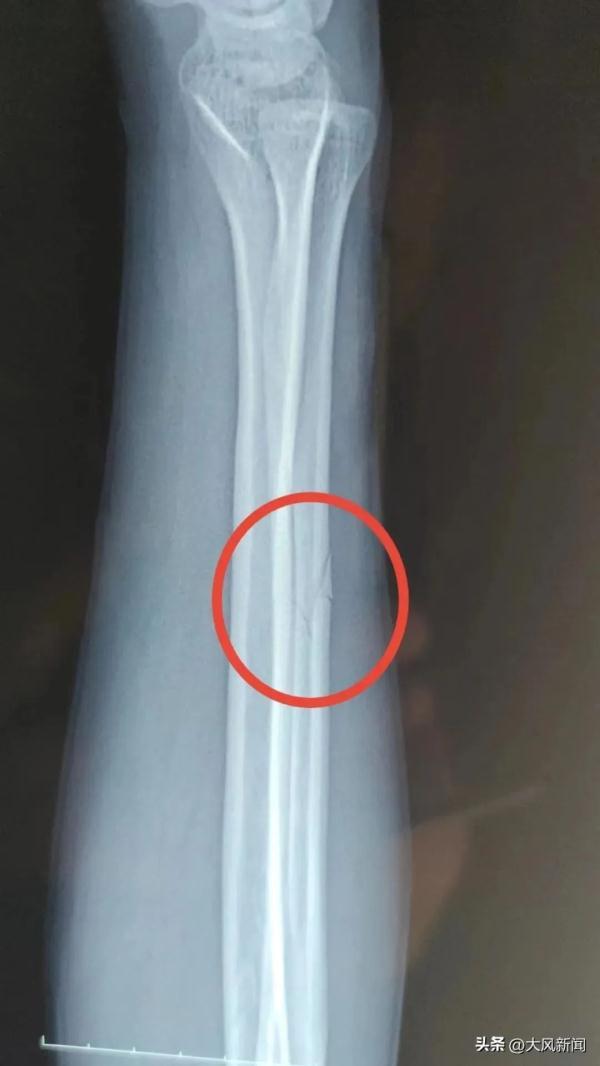

事发后宋某报了警,当晚去医院检查并打了石膏,医生让先回家观察。宋某系第二天右臂痛疼难忍,于2022年11月13日下午6时自行前往丹凤县医院检查。经诊断右尺骨骨折,外伤性头疼。